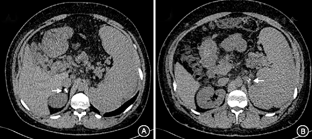

入院后相关检查,血常规:白细胞(2.53~4.01)×109/L,中性粒细胞(1.41~2.8)×109/L,血红蛋白152 g/L,血小板(71~100)×109/L;生化:总蛋白52 g/L,Alb <10 g/L(免疫比浊法1.77 g/L),前白蛋白347 mg/L,丙氨酸氨基转移酶29 U/L,肌酐68 μmol/L;总胆固醇7.60 mmol/L,甘油三酯2.65 mmol/L,低密度脂蛋白5.18 mmol/L,载脂蛋白B 1.57 g/L,游离脂肪酸72 μmol/L。凝血PT 21.3 s,APTT 63.7~100 s,纤维蛋白原3.89 g/L,D-二聚体1.19 mg/L;APTT(1∶1)纠正试验:APTT 81.4 s,APTT(纠正) 58.1 s。尿常规+沉渣(–);24 h尿蛋白0.05 g。便潜血(+);便苏丹Ⅲ染色(–);D-木糖吸收试验1.7 g。血渗透压298 mOsm/kgH2O。尿渗透529 mOsm/kgH2O。PPD(–),淋巴细胞+干扰素A+B 0 SFC 106MC。肿瘤标志物:甲胎蛋白33.8 μg/L,CA125 40.3 kU/L,余正常。免疫方面:红细胞沉降率21 mm/1 h,超敏C反应蛋白1.97 mg/L;IgG 20.82 g/L(升高↑),IgM 3.09 g/L↑,IgA 2.69 g/L;蛋白电泳Alb%14.4%(降低↓),白蛋白球蛋白比0.2,余升高;C3、C4正常;抗核抗体(ANA)斑点型(S)1∶1 280(+),抗ds-DNA、抗Sm(–);抗可溶性核抗原抗体、抗中性粒细胞胞质抗体(–)。狼疮抗凝物(LA) 2.05 s;抗心磷脂抗体(ACL) >120 PL IgG-KU/L,抗β2糖蛋白1(β2GP1) >200 000 RU/L。内分泌方面:促甲状腺激素6.504 mU/L↑,三碘甲状腺原氨酸4.22 nmol/L↑,甲状腺素17.30 nmol/L↑,游离三碘甲状腺原氨酸55.22 pmol/L,游离甲状腺素16.73 pmol/L。甲状过氧化物酶抗体81.26 kU/L↑,甲状腺球蛋抗体1 054.00 kU/L↑,促甲状腺素受体抗体<1 U/L。甲状旁腺素9.07 pmol/L;游离钙:1.13 mmol/L。ACTH 87.12 pmol/L↑。血皮质醇584.0 nmol/L。24 h尿皮质醇64.94 μg。(立位)血管紧张素-肾素-醛固酮系统:醛固酮58.17 nmol/L↓,肾素活性0.01 μg·L–1·h–1↓,血管紧张素Ⅱ 89.86 ng/L。抗肾上腺抗体阴性。尿电解质:K 22.6 mmol/L,Na 176 mmol/L,Cl 188 mmol/L。肾上腺CT:双侧肾上腺形态欠规则伴钙化影(图1);鞍区CT:未见明显异常。影像学检查:下肢深静脉彩超:右侧股浅静脉下段、腘静脉血栓形成。胸部CT:双肺下叶点片影及索条影,未见肿大淋巴结,双侧局部胸膜粘连。腹盆增强CT+小肠重建:回肠末端肠壁略厚,强化欠均匀;脾大;双侧肾上腺多发钙化;腹腔内少量积液;门脉异常改变;肠系膜区脂肪间隙模糊;皮下水肿。门静脉CT三维重建:考虑门静脉海绵样变性可能;胆囊窝迂曲血管团;脾静脉细、充盈欠均匀,陈旧血栓不除外,侧支开放;脾大;胆囊显示不清。腹盆CT动脉造影未见明显异常。胃镜:距门齿约32 cm以下,可见曲张静脉,呈蛇形,灰蓝色,最大直径约0.3 cm,未见红色征,胃底未见曲张静脉,胃角、胃窦黏膜呈褐色花斑样(含铁血红素沉积?),余黏膜红白相间,略显水肿十二指肠球部、球后及降部黏膜轻度肿胀,未见明显淋巴管扩张样改变。活检病理:(十二指肠降部)小肠黏膜显慢性炎,固有层水肿;(胃窦)胃黏膜显慢性炎。钡灌肠造影:结肠气钡双对比造影未见明显异常。(外院)肠失蛋白显像:未见蛋白丢失征象。最终诊断:抗磷脂抗体综合征(APS)、门静脉血栓、门静脉海绵样变性、食管胃底静脉曲张、脾大、脾梗死、腹水、右下肢深静脉血栓形成、慢性肺栓塞、Addison病、部分性肾上腺功能低减;先天性无白蛋白血症(CAA)可能性大,皮肤脂肪瘤;亚临床甲状腺功能减退、桥本甲状腺炎。治疗:入院后予以依诺肝素钠6 000 U每12 h 1次皮下注射,后序贯华法林3 mg每天1次抗凝治疗,监测国际标准化比值(INR) 2.3~2.6。2014年10月状况:患者无明显不适主诉,大便3~4次/d,为黄色稀便。体格检查:皮肤结节无明显变化,心肺听诊正常,腹围113 cm,移动性浊音(–);右小腿无明显水肿。

患者2006年发现皮肤变黑,有乏力、纳差,当地医院查血ACTH高,血皮质醇低,肾上腺占位,诊断Addison病。生理剂量糖皮质激素替代治疗有效,但是,患者近4年停药后无肾上腺皮质功能不全表现,与普通Addison病不同。患者2006年血ACTH达209.66 pmol/L,皮质醇降低;近期复查ACTH 87.12 pmol/L,血皮质醇及24 h尿游离皮质醇均正常,血钠、血糖为正常低限。Addison病在我国最常见病因为肾上腺结核,文献报道概率为60%~80%,多数起病隐匿,当肾上腺破坏>50%出现临床症状,随着肾上腺破坏加重,进一步出现肾上腺皮质功能不全、盐皮质激素分泌不足表现。本患者来自中国区县,肾上腺钙化明显,有Addison病,从概率上讲,需首先考虑肾上腺结核可能。但是,患者一般状况良好,无发热、盗汗、肺部病变等结核感染表现,PPD及淋巴细胞+干扰素均阴性,患者肾上腺破坏不明显,与结核不符,尚需考虑其他原因所致肾上腺钙化可能。西方国家Addison病最常见病因为结缔组织病(CTD),自身免疫性肾上腺炎肾上腺多萎缩少数钙化,且多伴有其他免疫性疾病。此患者亦有自身免疫性甲状腺炎、APS,考虑CTD可能。患者有多发静脉血栓形成,APS导致肾上腺血管血栓或出血梗死后机化可致肾上腺钙化,Pubmed数据库检索APS合并Addison病报道,文献中有部分、单侧、双侧肾上腺梗死等表现。复习文献,可知APS为Addison病的少见病因,Addison病可以为APS的首发表现[1],文献中,大部分患者肾上腺功能无恢复,少数可见肾上腺功能部分恢复,可能与肾上腺血供丰富有关。本患者临床表现及实验室检查均可诊断原发性肾上腺功能减退,但是,其肾上腺功能并无进行性下降,表现为部分性肾上腺皮质功能低减,病因考虑APS可能性大。目前尚不需激素替代治疗,随诊过程中应定期检测血皮质醇水平,嘱咐患者若遇应激事件,需及时补充皮质醇。